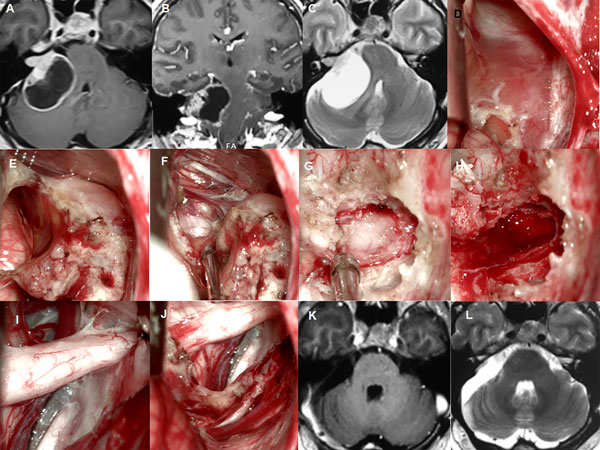

Figura 2: Paciente masculino de 59 años, operado de SV T1 izquierdo. A-C: RM preoperatoria. D-I: hallazgos intraoperatorios. J-L: RM postoperatoria.